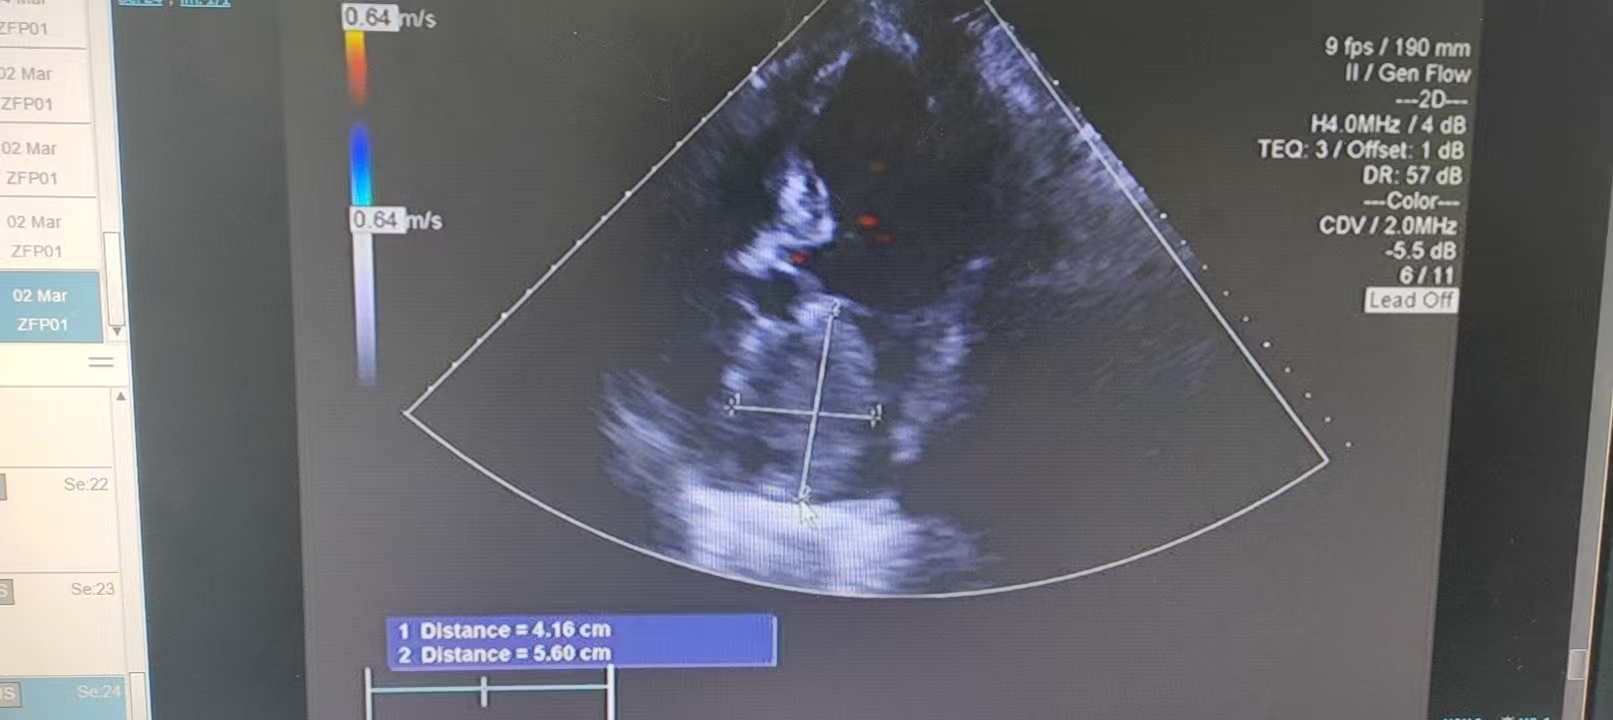

据悉,这位70余岁的李奶奶,近半年来一直被严重的胸闷、气促症状困扰,日常活动稍受影响便喘憋难忍,甚至连平卧都十分困难,只能不断调整体位才能稍稍缓解不适,生活质量急剧下降。随着症状愈发严重,家人陪同老人前往我院就诊,经心脏超声检查后,结果让所有人都揪心不已:老人的左心房内生长着一个约5x6厘米的巨大黏液瘤,大小如同一枚土豆,几乎填满了整个左心房空间,严重挤占了心脏的正常空间。